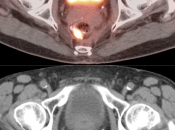

Presentation of Primary Cancer:

- Focal bowel uptake, usually with associated bowel wall thickening.

- If long-segment, think inflammation.

- If diffuse, usually normal physiologic uptake.

- Beware the small rectal cancer! As the ano-rectal region frequently demonstrates intense physiologic uptake, it is very easy to overlook a rectal malignancy, especially if it is an incidental finding. To avoid this error, always evaluate the rectum carefully on the sagittal whole body images. It is shocking to see how readily apparent a rectal cancer can be on these images, yet so easily overlooked in the axial plane.